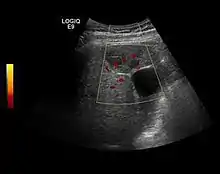

US examination is required to detect liver metastases in patients with oncologic history. In addition, the method can incidentally detect metastases in asymptomatic patients. Early identification (small sizes, small number) is important to establish an optimal course of treatment which can be complex (chemotherapy, radiofrequency ablation, surgical resection) but welcomed. In addition, discrimination of synchronous lesions that have a different nature is also important knowing that up to 25–50% of liver lesions less than 2 cm detected in cancer patients may be benign . US sensitivity for metastases detection varies depending on the examiner's experience and the equipment used and ranges between 40–80% . Sensitivity is conditioned by the size and acoustic impedance of the nodules. For a lesion diameter below 10 mm US accuracy is greatly reduced, reaching approx. 20%. Other elements contributing to lower US performance are: excessive obesity, fatty liver disease, hypomobility of the diaphragm, and certain patterns of hyperechoic or isoechoic metastases that can be overlooked or can mimic benign conditions. Conventional US appearance of metastases is uncharacteristic, consisting of circumscribed lesions, with clear, imprecise or "halo" delineation, with homogeneous or heterogeneous echo pattern. They can be single (often liver metastases from colonic neoplasm) or multiple. Echogenity is variable. When increased, they can compress the bile ducts (which may be dilated) and the liver vessels. Liver involvement can be segmental, lobar or generalized. In this situation a pronounced hepatomegaly occurs. Generally, metastases have non-characteristic Doppler vascular pattern, with few exceptions (carcinoid metastases). Cyst-adenocarcinoma metastases due to semifluid content may have a transonic appearance. When increasing, they can result in central necrosis. CEUS examination is a real breakthrough for detection and characterization of liver metastases.

Increased performance is based on identifying specific vascular patterns during the arterial phase and seeing metastases in contrast to normal liver parenchyma during the sinusoidal phase. CEUS increased accuracy is due to the different behavior of normal liver parenchyma (captures CA in Kuppfer cells) against tumor parenchyma (does not contain Kuppfer cells, therefore CEUS appearance is hypoechoic). To this adds the particularities of intratumoral circulation represented by a reduced arterial bed compared to that of the surrounding normal liver and the absence of the portal vessels . In terms of vascularity, metastases can be hypovascular (in gastric, colonic, pancreatic or ovarian adenocarcinomas) with hypoechoic pattern during arterial phase, and similar during portal venous and late phases, respectively hypervascular (neuroendocrine tumors, malignant melanoma, sarcomas, renal, breast or thyroid tumors) with hyperechoic appearance during arterial phase, with washout during the portal venous phase and hypoechoic pattern 30 seconds after injection.